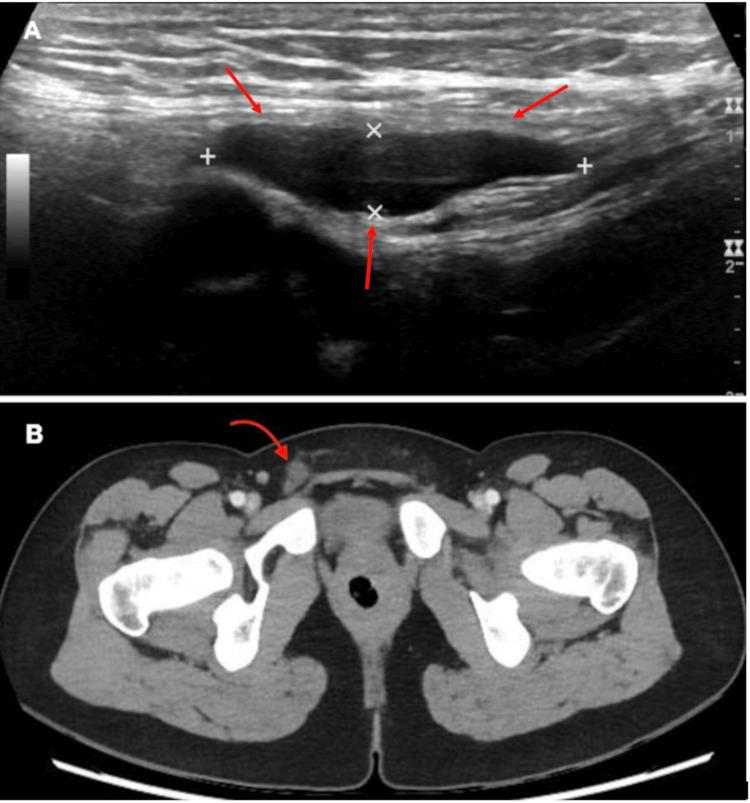

Nuck's canal is the incomplete obliteration of the processus vaginalis, and it is a rare condition that should consider inguinodynia and an increased volume in the inguinal region as a differential diagnosis. Endometriosis is a systemic disease that affects young women. This condition has many clinical presentations, and it is exceptional to find it associated with a Nuck's canal cyst. We present the case of a 20-year-old woman who presented with right inguinal pain associated with increased volume. An inguinal ultrasound and abdominopelvic computed tomography (CT) were performed, and a right Nuck's canal cyst was diagnosed. The condition was managed surgically with resection of the Nuck's canal cyst and transabdominal preperitoneal plasty (TAPP) for inguinal hernia laparoscopic reconstruction, with a satisfactory outcome.

努克管是鞘突未完全闭锁,这是一种罕见情况,鉴别诊断时应考虑腹股沟疼痛和腹股沟区肿物增大。子宫内膜异位症是一种影响年轻女性的全身性疾病。这种疾病有多种临床表现,与努克管囊肿相关的情况很罕见。我们报告一例20岁女性,她因右侧腹股沟疼痛伴肿物增大前来就诊。进行了腹股沟超声和腹盆腔计算机断层扫描(CT)检查,诊断为右侧努克管囊肿。通过手术切除努克管囊肿并采用经腹腹膜前修补术(TAPP)进行腹腔镜下腹股沟疝重建,治疗效果满意。